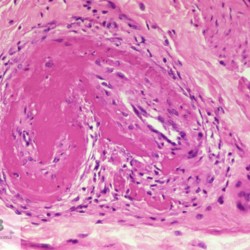

Etiquetes: N-90/90 de 2 Pàgina següent 9 total Canine Specie: Canine Organ: Stomach Lesion: Vasculitis Lesion modifier: - Disease: Leishmaniasis Files/Expedient: N-90/90 Not viewed Canine Specie: Canine Organ: Stomach Lesion: Vasculitis Lesion modifier: - Disease: Leishmaniasis Files/Expedient: N-90/90 Not viewed Canine Specie: Canine Organ: Intestine Lesion: Vasculitis Lesion modifier: - Disease: Leishmaniasis Files/Expedient: N-90/90 Not viewed Canine Specie: Canine Organ: Urinay bladder Lesion: Vasculitis Lesion modifier: - Disease: Leishmaniasis Files/Expedient: N-90/90 Not viewed Canine Specie: Canine Organ: Heart Lesion: Vasculitis Lesion modifier: - Disease: Leishmaniasis Files/Expedient: N-90/90 Not viewed de 2 Pàgina següent Títol Select...Avian (Exotic) (110)Avian (Poultry) (76)Bovine (317)Canine (935)Caprine (47)Equine (257)Feline (326)Ferret (19)General (127)Marine mammal (22)Non-human primate (20)Ovine (328)Porcine (379)Rabbit (61)Reptile (38)Rodent (28)Wildlife (91) Format Select...- (60)Abomasum (37)Adrenal gland (10)Blood (7)Blood vessel (50)Body as a whole (19)Bone (57)Bone marrow (21)Brain (93)Cloaca (1)Diaphragm (2)Ear (5)Esophagus (39)Eye (16)Fetus (12)Gallbladder (23)Gizzard (2)Heart (265)Intestine (356)Joint (32)Kidney (443)Larynx (5)Liver (326)Lung (264)Lymph node (91)Mammary gland (10)Mediastinum (1)Muscle (22)Nasal cavity (22)Nerve (7)Omasum (5)Oral cavity (63)Ovary (14)Oviduct (8)Pancreas (7)Parathyroid (5)Penis (10)Peritoneum (65)Pharynx (9)Pituitary gland (6)Placenta (7)Prostate (8)Proventriculus (3)Reticulum (1)Rumen (28)Sinus (7)Skin (181)Spinal cord (15)Spleen (105)Stomach (125)Teeth (1)Testicle (11)Thoracic cavity (31)Thymus (13)Thyroid gland (5)Tongue (32)Tonsils (11)Trachea (11)Urethra (5)Urinay bladder (61)Uterus (27)Vagina (1)Vulva (1)Yolk sac (1) Cobertura Select...- (152)Abomasitis (26)Abscess (27)Acidosis (1)Adenocarcinoma (20)Adenoma (9)Aerosacculitis (6)Agenesis (1)Agnathia (1)Alopecia (7)Amyloidosis (12)Aneurysm (6)Angiectasis (1)Anthracosis (1)Arteritis (11)Arthritis (15)Arthrogryposis (6)Artifact (4)Ascites (13)Atelectasis (8)Atherosclerosis (5)Atresia (1)Atrial septal defect (2)Atrophy (10)Autolysis (7)Bronchitis (6)Bronchopneumonia (26)Cachexia (2)Carcinoma (103)Cardiomyopathy (19)Cellulitis (2)Chemodectoma (4)Cholangiohepatitis (4)Cholangitis (19)Cholecystitis (4)Cholestasis (5)Chondrodysplasia (2)Chondrosarcoma (2)Chronic passive congestion (13)Chylothorax (2)Cirrhosis (6)Coelomitis (3)Coenurus cerebralis (4)Colitis (40)Congestion (17)Conjunctivitis (5)Coronitis (3)Cryptorchidism (3)Cyst (25)Cystitis (24)Dermatitis (69)Diaphragmatic hernia (4)Dilation (28)Discospondylitis (1)Disseminated intravascular coagulation (7)Dyschondroplasia (1)Dysplasia (29)Ectopia cordis (1)Ectopic ureter (1)Edema (55)Emphysema (5)Encephalitis (5)Endocardiosis (14)Endocarditis (26)Endometritis (5)Enteritis (118)Enterolith (6)Epulis (3)Esophagitis (14)Fasciitis (1)Fibrosis (7)Fibrous osteodystrophy (8)Fistula (1)Folliculitis (3)Fracture (2)Gastritis (34)Gingivitis (5)Glioma (8)Glomerulonephritis (21)Glossitis (25)Glycogenosis (1)Gout (8)Granuloma (2)Granulosa cell tumor (4)Hemangioma (9)Hemangiosarcoma (46)Hematoma (8)Hemoglobinuria (2)Hemopericardium (12)Hemoperitoneum (2)Hemorrhage (100)Hemosiderosis (7)Hemothorax (2)Hepatitis (78)Hernia (11)Histiocytosis (3)Hydatid cyst (11)Hydrocephalus (9)Hydrometra (1)Hydronephrosis (22)Hydropericardium (6)Hydrothorax (3)Hydroureter (5)Hyperkeratosis (8)Hyperostosis (4)Hyperplasia (37)Hypertrophy (9)Hypopigmentation (1)Hypoplasia (7)Hypopyon (1)Impaction (6)Infarction (63)Insulinoma (6)Intussusception (5)Jaundice (17)Laminitis (2)Laryngitis (2)Leiomyoma (5)Leukemia (13)Lipidosis (36)Lipoma (7)Lymphadenitis (45)Lymphadenopathy (7)Lymphangiectasia (6)Lymphangitis (5)Lymphoma (221)Malacia (11)Malignant melanoma (15)Mast cell tumor (11)Mastitis (8)Megaesophagus (2)Melanosis (3)Melena (4)Meningioma (6)Meningitis (6)Meningocele (2)Meningoencephalitis (5)Mesothelioma (5)Methemoglobinemia (2)Mineralization (10)Mucocele (5)Mucometra (1)Multilobular bone tumor (1)Mummification (3)Myelofibrosis (1)Myocarditis (4)Myositis (5)Necrosis (81)Nephritis (113)Nephroblastoma (6)Nephrosclerosis (1)Nephrosis (14)Neuritis (1)Obstruction (13)Omasitis (4)Omphalitis (1)Omphalophlebitis (7)Orchitis (4)Osteoarthrosis (5)Osteomyelitis (9)Otitis (2)Palatoschisis (3)Pancreatitis (3)Panniculitis (3)Papilloma (7)Parakeratosis (14)Patent ductus arteriosus (6)Peliosis hepatis (1)Perforation (17)Pericarditis (35)Peritonitis (39)Persistent right aortic arch (1)Pharyngitis (2)Pheochromocytoma (2)Phlebitis (2)Placentitis (6)Pleuritis (21)Pleuropneumonia (24)Pneumonia (109)Pneumothorax (3)Polycystosis (14)Polyp (5)Polyserositis (6)Posthitis (1)Proctitis (4)Prolapse (3)Prostatitis (3)Proventriculitis (1)Pyelonephritis (24)Pyometra (6)Pyothorax (4)Rhinitis (11)Rumenitis (6)Rupture (24)Salpingitis (3)Sarcoma (57)Sclerosis (1)Scoliosis (2)Seminoma (2)Sequestrum (2)Serous atrophy (14)Sinusitis (7)Splenitis (14)Splenomegaly (9)Spondylitis (6)Spondylosis (1)Stenosis (9)Stomatitis (32)Tenosynovitis (2)Teratoma (3)Thricobezoar (2)Thrombosis (16)Tonsilitis (4)Torsion (13)Tracheitis (4)Tympany (7)Typhlitis (8)Typhlocolitis (4)Ulcer (43)Urethritis (1)Urolithiasis (36)Uroperitoneum (1)Uveitis (1)Vasculitis (15)Ventricular septal defect (3)Volvulus (11) Matèria Select... - (14)- (1653)- (152)Abomasitis - Catarrhal (2)Abomasitis - Catarrhal-hemorrhagic (1)Abomasitis - Chronic (1)Abomasitis - Fibrinous-necrotizing (2)Abomasitis - Hyperplasic (5)Abomasitis - Hyperplasic - Chronic (1)Abomasitis - Necrotic (1)Abomasitis - Necrotizing (2)Abomasitis - Ulcerative (5)Adenocarcinoma (9)Aerosacculitis - Granulomatous (1)Amyloidosis - Chronic (1)Arteritis - Necrotic (2)Arteritis - Necrotizing (1)Arthritis - Chronic (4)Arthritis - Fibrinous-purulent (3)Arthritis - Serous (4)Arthritis - Subacute (1)Ascites - Serous (1)Atrophy - Serous (1)Bronchitis - Catarrhal (3)Bronchitis - Suppurative (1)Bronchopneumonia - Catarrhal-purulent (17)Bronchopneumonia - Fibrinous (1)Bronchopneumonia - Granulomatous (1)Bronchopneumonia - Purulent (1)Bronchopneumonia - Suppurative (5)Carcinoma - Adenocarcinoma (33)Carcinoma - Adenocarcinoma - Hepatocellular (2)Carcinoma - Adenocarcinoma - Mucinous (1)Carcinoma - Basosquamous (1)Carcinoma - Cholangiocellular (3)Carcinoma - Hepatocellular (4)Carcinoma - Metastatic (3)Carcinoma - Squamous cell carcinoma (13)Carcinoma - Transitional cell (2)Cardiomyopathy - Dilated (13)Cardiomyopathy - Hypertrophic (6)Cellulitis - Necrotizing (1)Cholangitis - Chronic (8)Cholangitis - Hyperplasic (3)Cholecystitis - Fibrinous-necrotizing (1)Coelomitis - Fibrinous (1)Coelomitis - Granulomatous (1)Colitis - Catarrhal (3)Colitis - Catarrhal-hemorrhagic (1)Colitis - Fibrinous (1)Colitis - Fibrinous-necrotizing (1)Colitis - Fibrinous-necrotizing (Diphtheritic) (6)Colitis - Granulomatous (2)Colitis - Hemorrhagic (4)Colitis - Hemorrhagic-necrotizing (3)Colitis - Necrotizing (2)Colitis - Ulcerative (6)Congestion - Chronic (2)Conjunctivitis - Hyperplasic (1)Conjunctivitis - Purulent (3)Coronitis - Ulcerative (1)Cystitis - Chronic (3)Cystitis - Fibrinous (1)Cystitis - Fibrinous-necrotizing (1)Cystitis - Follicular (1)Cystitis - Hemorrhagic (6)Cystitis - Hemorrhagic-ulcerative (1)Cystitis - Necrotizing (9)Cystitis - Perforated (1)Dermatitis - Granulomatous (14)Dermatitis - Hyperkeratotic (10)Dermatitis - Hyperplasic (proliferative) (1)Dermatitis - Hyperplastic (10)Dermatitis - Necrotizing (4)Dermatitis - Pustular (4)Dermatitis - Ulcerative (2)Dilation - Chronic (1)Discospondylitis - Necrotizing (1)Dysplasia - Follicular (5)Edema - Interstitial (6)Emphysema - Interstitial (1)Encephalitis - Granulomatous (1)Encephalitis - Nonsuppurative (1)Endocardiosis - Mitral (7)Endocardiosis - Mitral - Chronic (5)Endocarditis - Valvular (6)Endocarditis - Valvular - Mitral (7)Endocarditis - Valvular - Pulmonic (1)Endocarditis - Valvular - Subacute (1)Endocarditis - Valvular - Subaortic (5)Endocarditis - Valvular - Tricuspid (4)Endometritis - Purulent (3)Endometritis - Purulent-hemorrhagic (2)Enteritis - Catarrhal (23)Enteritis - Catarrhal - Acute (1)Enteritis - Catarrhal-hemorrhagic (5)Enteritis - Catarrhal-hemorrhagic - Acute (2)Enteritis - Fibrinous (16)Enteritis - Fibrinous - Acute (3)Enteritis - Fibrinous-necrotizing (7)Enteritis - Granulomatous (14)Enteritis - Granulomatous - Chronic (1)Enteritis - Granulomatous - Multifocal (1)Enteritis - Hemorrhagic (17)Enteritis - Hemorrhagic - Acute (1)Enteritis - Hemorrhagic-necrotizing (1)Enteritis - Hyperplasic (proliferative) (4)Enteritis - Necrotizing (4)Enteritis - Necrotizing - Acute (1)Enteritis - Necrotizing - Hemorrhagic (1)Enteritis - Necrotizing-ulcerative (2)Enteritis - Ulcerative (1)Enteritis - Ulcerative-hemorrhagic (1)Esophagitis - Erosive-ulcerative (6)Esophagitis - Necrotizing (4)Esophagitis - Ulcerative (1)Esophagitis - Ulcerative-necrotizing (1)Fasciitis - Fibrinous-purulent (1)Folliculitis - Purulent (2)Gastritis - Catarrhal (2)Gastritis - Chronic (1)Gastritis - Follicular (1)Gastritis - Hemorrhagic (2)Gastritis - Hemorrhagic-necrotizing (1)Gastritis - Hypertrophic (2)Gastritis - Inclusion bodies (1)Gastritis - Mineralization (1)Gastritis - Mycotic (1)Gastritis - Necrotizing (2)Gastritis - Ulcerative (6)Gastritis - Uremic (3)Gingivitis - Erosive (2)Gingivitis - Hyperplasic (proliferative) (1)Gingivitis - Necrotizing (1)Glomerulonephritis - Chronic (7)Glomerulonephritis - Membranoproliferative (3)Glomerulonephritis - Membranoproliferative - Chronic (1)Glomerulonephritis - Membranous (3)Glomerulonephritis - Membranous - Chronic (1)Glomerulonephritis - Proliferative (2)Glomerulonephritis - Subacute (1)Glossitis - Erosive (2)Glossitis - Granulomatous (6)Glossitis - Hyperplasic (1)Glossitis - Hyperplasic (proliferative) (2)Glossitis - Hyperplastic (1)Glossitis - Necrotizing (2)Glossitis - Necrotizing - Focal (1)Glossitis - Ulcerative (6)Glossitis - Ulcerative - Multifocal (1)Glossitis - Ulcerative - Subacute (1)Glycogenosis (1)Granuloma - Eosinophilic (1)Hemangiosarcoma - Metastatic (2)Hemorrhage - Acute (1)Hemorrhage - Subcapsular (3)Hepatitis - Abscess (9)Hepatitis - Acute (3)Hepatitis - Chronic (4)Hepatitis - Chronic interstitial (6)Hepatitis - Granulomatous (7)Hepatitis - Interstitial - Multifocal (1)Hepatitis - Interstitial - Subacute (1)Hepatitis - Necrotizing (17)Hepatitis - Necrotizing - Acute (2)Hepatitis - Necrotizing - Hemorrhagic (1)Hepatitis - Necrotizing - Subacute (1)Hepatitis - Pyogranulomatous (7)Hepatitis - Subacute (4)Hydronephrosis - Chronic (1)Hydropericardium - Chronic (1)Hyperplasia - Erythroid (1)Hyperplasia - Lymphoid (3)Hyperplasia - Myeloid (1)Hyperplasia - Nodular (8)Hypertrophy - Concentric (2)Hypertrophy - Eccentric (3)Infarction - Acute (17)Infarction - Acute - Multifocal (2)Infarction - Chronic (5)Infarction - Chronic - Multifocal (1)Infarction - Subacute (18)Infarction - Subacute - Focal (2)Laminitis - Chronic (2)Laryngitis - Necrotic (1)Laryngitis - Necrotizing (1)Leukemia - Lymphoid leukemia (2)Leukemia - Non-lymphoid leukemia (6)Lipidosis - Multifocal (1)Lipidosis - Panlobular (1)Lipidosis - Panlobular - Generalized (2)Lymphadenitis - Granulomatous (24)Lymphadenitis - Granulomatous - Chronic (3)Lymphadenitis - Hemorrhagic (1)Lymphadenitis - Necrotizing (5)Lymphadenitis - Necrotizing (caseous) (11)Lymphangitis - Granulomatous (1)Lymphangitis - Purulent (1)Lymphangitis - Ulcerative (1)Lymphoma - Alimentary lymphoma (7)Lymphoma - Cutaneous lymphoma (6)Lymphoma - Lymphosarcoma (2)Lymphoma - Mediastinal lymphoma (1)Lymphoma - Multicentric lymphoma (29)Malignant melanoma - Malignant (1)Malignant melanoma - Metastatic (1)Mast cell tumor - Metastatic (1)Mastitis - Fibrinous-purulent (2)Mastitis - Necrotic (1)Mastitis - Purulent (3)Mastitis - Suppurative (1)Meningitis - Fibrinous-purulent (2)Meningitis - Purulent (4)Meningoencephalitis - Necrotizing (3)Meningoencephalitis - Nonsuppurative (2)Mineralization - Metastatic (4)Myocarditis - Fibrous - Chronic (1)Myocarditis - Granulomatous (1)Myositis - Purulent (2)Necrosis - Acute (1)Necrosis - Cortical (5)Necrosis - Follicular (1)Necrosis - Papillary (8)Necrosis - Papillary - Acute (3)Necrosis - Subacute (3)Necrosis - Tubular (6)Nephritis - Embolic (2)Nephritis - Embolic suppurative (7)Nephritis - Granulomatous (27)Nephritis - Granulomatous - Chronic (1)Nephritis - Granulomatous - Multifocal (1)Nephritis - Interstitial (6)Nephritis - Interstitial - Acute (4)Nephritis - Interstitial - Chronic (41)Nephritis - Interstitial - Subacute (12)Nephritis - Purulent (7)Nephritis - Purulent - Acute (2)Nephritis - Purulent - Multifocal (3)Nephrosis - Cholemic (3)Nephrosis - Hemoglobinuric (10)Omasitis - Fibrinous-necrotizing (1)Omasitis - Hyperkeratotic (1)Omasitis - Necrotizing (2)Omphalophlebitis - Fibrinous-purulent (2)Omphalophlebitis - Purulent (3)Orchitis - Necrotizing (1)Osteomyelitis - Necrotizing (7)Osteomyelitis - Purulent (2)Otitis - Necrotizing (1)Otitis - Proliferative (1)Pancreatitis - Acute (1)Pancreatitis - Chronic (1)Pancreatitis - Granulomatous (1)Panniculitis - Fibrinous-purulent (1)Panniculitis - Necrotic (1)Panniculitis - Parasitic (1)Perforation - Acute (2)Pericarditis - Fibrinous (19)Pericarditis - Fibrinous - Subacute (1)Pericarditis - Fibrinous-necrotizing (1)Pericarditis - Fibrinous-purulent (3)Pericarditis - Fibrous (1)Pericarditis - Fibrous - Chronic (1)Pericarditis - Gangrenous (6)Pericarditis - Granulomatous (1)Pericarditis - Granulomatous - Chronic (2)Peritonitis - Acute (1)Peritonitis - Fibrinous (11)Peritonitis - Fibrinous - Subacute (1)Peritonitis - Fibrinous-purulent (5)Peritonitis - Fibrous (3)Peritonitis - Granulomatous (6)Peritonitis - Purulent (1)Peritonitis - Purulent-hemorrhagic (1)Peritonitis - Pyogranulomatous (3)Pharyngitis - Fibrinous-necrotizing (1)Pharyngitis - Ulcerative (1)Pheochromocytoma - Metastatic (1)Phlebitis - Purulent (1)Placentitis - Fibrinous-necrotizing (1)Placentitis - Necrotic (1)Placentitis - Necrotizing (1)Pleuritis - Chronic (1)Pleuritis - Fibrinous (3)Pleuritis - Fibrinous-purulent (2)Pleuritis - Fibrous (2)Pleuritis - Granulomatous (3)Pleuritis - Hyperplastic (2)Pleuritis - Purulent (2)Pleuritis - Pyogranulomatous (1)Pleuropneumonia - Fibrinous (13)Pleuropneumonia - Fibrinous-necrotizing (5)Pleuropneumonia - Granulomatous (2)Pleuropneumonia - Hemorrhagic-necrotizing (4)Pneumonia - Aspiration (11)Pneumonia - Bronchointerstitial (4)Pneumonia - Bronchointerstitial - Subacute (1)Pneumonia - Embolic (5)Pneumonia - Granulomatous (37)Pneumonia - Granulomatous - Multifocal (4)Pneumonia - Hemorrhagic-necrotizing (2)Pneumonia - Interstitial (7)Pneumonia - Interstitial - Acute (8)Pneumonia - Interstitial - Chronic (6)Pneumonia - Interstitial - Subacute (15)Pneumonia - Necrotizing (2)Pneumonia - Pyogranulomatous (2)Pneumonia - Verminous (5)Polyserositis - Fibrinous (6)Polyserositis - Fibrous (1)Proctitis - Fibrinous-necrotizing (1)Proctitis - Parasitic (2)Prostatitis - Purulent (1)Pyelonephritis - Acute (2)Pyelonephritis - Chronic (3)Rhinitis - Catarrhal (2)Rhinitis - Fibrinous (1)Rhinitis - Granulomatous (4)Rhinitis - Purulent (3)Rumenitis - Acute (1)Rumenitis - Erosive (1)Rumenitis - Necrotizing (1)Rupture - Acute (3)Sarcoma - Fibrosarcoma (12)Sarcoma - Hemangiosarcoma (11)Sarcoma - Histiocytic (7)Sarcoma - Metastatic (1)Sarcoma - Multilobular tumor of bone (1)Sequestrum - Chronic (2)Sinusitis - Suppurative (1)Splenitis - Granulomatous (8)Splenitis - Granulomatous - Chronic (1)Splenitis - Necrotizing (3)Splenitis - Necrotizing (caseous) (2)Spondylitis - Necrotizing (2)Stenosis - Intestinal (1)Stenosis - Valvular - Subaortic (4)Stomatitis - Erosive (12)Stomatitis - Erosive-ulcerative (3)Stomatitis - Fibrinous-necrotizing (1)Stomatitis - Fibrinous-necrotizing (Diphtheritic) (1)Stomatitis - Granulomatous (1)Stomatitis - Hyperplasic (1)Stomatitis - Hyperplasic (proliferative) (1)Stomatitis - Necrotizing (2)Stomatitis - Ulcerative (5)Stomatitis - Ulcerative - Multifocal (1)Stomatitis - Ulcerative-necrotizing (1)Tonsilitis - Necrotizing (4)Torsion - Acute passive hyperemia (5)Tracheitis - Catarrhal (3)Tracheitis - Fibrinous (1)Tracheitis - Granulomatous (1)Typhlitis - Catarrhal (1)Typhlitis - Fibrinous-necrotizing (2)Typhlitis - Hemorrhagic (2)Typhlitis - Ulcerative-hemorrhagic (1)Typhlocolitis - Fibrinous-necrotizing (2)Typhlocolitis - Proliferative (1)Ulcer - Chronic (6)Ulcer - Multifocal (2)Ulcer - Mycotic (1)Ulcer - Perforated (6)Urethritis - Hemorrhagic (1)Urolithiasis - Chronic (2)Uveitis - Granulomatous (1)Vasculitis - Granulomatous (1)Vasculitis - Necrotizing (1) Editor Select...- (1970)Acidosis (2)Actinobacillosis (Pleuropneumonia) (11)Aelurostrongylosis (2)African horse sickness (13)African swine fever (14)Alopecia X (1)Anaplasmosis (4)Anthrax (2)Aortic thromboembolism (feline) (7)Ascariasis (15)Aspergillosis (18)Atopic dermatitis (1)Atrophic rhinitis (3)Babesiosis (6)Blackhead (1)Bluetongue (11)Border disease (2)Bovine viral diarrhea (21)Brucellosis (2)Candidiasis (5)Canine distemper (14)Caprine arthritis-encephalitis (2)Capture myopathy (1)Cardiac insufficiency (17)Caseous lymphadenitis (7)Chlamydiosis (2)Classical swine fever (19)Clostridiosis (19)Coccidiosis (9)Coenurosis (4)Colibacillosis (21)Contagious ecthyma (7)Copper toxicosis (11)Cowdriosis (Heartwater) (3)Cryptococcosis (3)Cryptosporidiosis (2)Cysticercosis (23)Demodicosis (1)Diabetes (1)Dicrocoeliosis (5)Dictyocaulosis (4)Dirofilariasis (7)Discoid lupus erythematosus (3)Echinococcosis (17)Edema disease (7)Egg drop syndrome (1)Encephalitozoonosis (5)Enterotoxemia (1)Enzootic bovine leukosis (46)Epitheliogenesis imperfecta (3)Equine rhinopneumonitis (2)Equine verminous arteritis (strongylosis) (7)Erysipelas (5)Exudative epidermitis (7)Fasciolasis (11)Feline eosinophilic dermatoses (1)Feline hepatic lipidosis (8)Feline histiocytosis (4)Feline infectious peritonitis (38)Feline leukemia (4)Feline lower urinary tract disease (3)Feline panleukopenia (16)Feline viral rhinotracheitis (1)Flea allergy dermatitis (1)Foot and mouth disease (2)Gasterophilosis (4)Glasser's disease (15)Gousiekte (4)Gout (6)Haemonchosis (9)Hemolytic anemia (4)Hemorrhagic diathesis (1)Hepatic insufficiency (11)Hepatosis dietetica (7)Herpesvirosis (6)Hyperadrenocorticism (7)Hyperparathyroidism (10)Hypertrophic osteopathy (6)Hypervitaminosis D (1)Hypodermosis (1)Inclusion body hepatitis (4)Infectious bovine rhinotracheitis (5)Infectious bronchitis (5)Infectious canine hepatitis (13)Influenza (4)Juvenile nephropathy (8)Lamb dysentery (4)Leishmaniasis (28)Leptospirosis (1)Leukosis (5)Listeriosis (4)Lumpy skin disease (3)Maedi-visna (4)Malignant catarrhal fever (12)Mange (6)Mannheimiosis (5)Marek's disease (7)Metabolic bone disease (2)Mucoid enteropathy (5)Mulberry heart disease (5)Myasis (1)Mycobacteriosis (22)Mycosis fungoides (6)Myxomatosis (3)Necrobacillosis (5)Neonatal isoerythrolysis (6)Nocardiosis (4)Oestrosis (2)Onchocerciasis (1)Osteochondrosis (1)Ostertagiosis (6)Ovine pulmonary adenocarcinoma (5)Oxyuriasis (1)Pacheco's disease (4)Papillomatosis (6)Paratuberculosis (18)Parvovirosis (17)Pasteurellosis (11)Pemphigus foliaceus (1)Periodontal disease (1)Polioencephalomalacia of ruminants (4)Polyarteritis nodosa (3)Polycystic kidney disease (13)Porcine circovirosis (11)Porcine dermatitis and nephropathy syndrome (9)Porcine proliferative enteropathy (4)Porcine reproductive and respiratory syndrome (6)Porcine stress syndrome (1)Pox (13)Pregnancy toxemia (3)Proventricular dilatation disease (2)Pseudotuberculosis (yersiniosis) (2)Psittacine beak and feather disease (PBFD) (5)Pyoderma (4)Q fever (4)Rabbit hemorrhagic disease (2)Renal insufficiency (12)Reticuloendotheliosis (2)Rhodococcosis (1)Rickets (1)Rinderpest (2)Salmonellosis (34)Sarcosporidiosis (2)Schmallenberg (7)Septicemia (23)Spirocercosis (11)Streptococcosis (5)Strongylosis (1)Swine dysentery (5)Systemic coronavirosis (5)Tetralogy of Fallot (5)Theileriosis (13)Thromboembolism (5)Toxoplasmosis (11)Transmissible viral proventriculitis (1)Traumatic reticuloperitonitis (3)Traumatism (16)Tuberculosis (58)Ulcerative lymphangitis (1)Uremic syndrome (20)Viral arthritis (6)White muscle disease (9)Wobbler syndrome (2)Xanthomatosis (1)Zygomycosis (4) Idioma Select...- (1180)Bacterial (501)Degeneration (106)Fungal (46)Hemodynamic (112)Idiopathic (22)Inflammation (58)Malformation (88)Neoplasia (343)Nutritional (41)Parasitic (243)Physical/Chemical (93)Toxic (44)Viral (304) Ítem destacat Avian (Poultry) Broilers. Livers are swollen, pale, friable with petechial or echymotic hemorrhages. Adenovirus (group I).